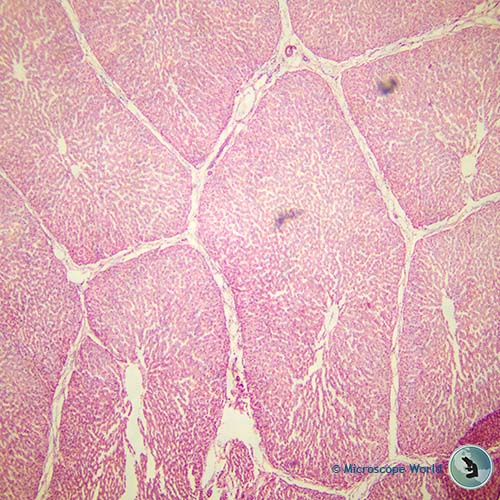

Pig liver, 40x |